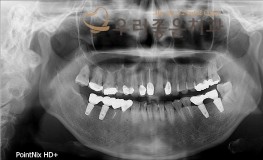

우리좋은치과 치아 상실로 인한 임플란트 보철 치료 (최** 2019.02.20~07..

No.347

임플란트

2019-11-25

1568